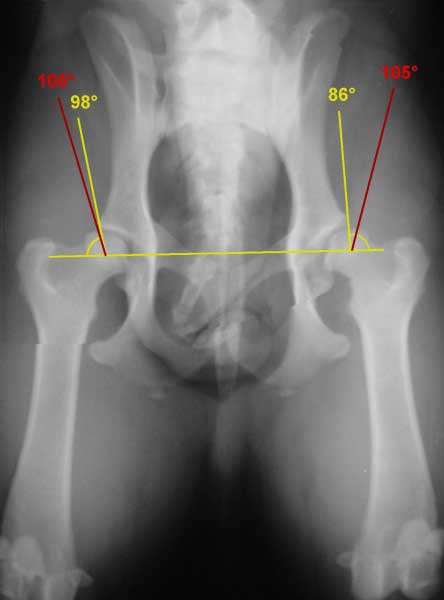

Norberg WinkelEin wesentliches Kriterium für die Auswertung ist der Norberg-Winkel. Er ist als der Winkel definiert, der zwischen dem Zentrum des Oberschenkel-kopfes und dem vorderen Pfannenrand abgetragen wird. Bei einem HD-freien Tier sollte er mehr als 105° betragen (rote Linien).

A: HD-Frei In jeder Hinsicht unauffällige Gelenke, Norberg-Winkel 105° oder mehr. Manchmal noch A1 wenn der Pfannenrand den Oberschenkelknochen noch weiter umgreift.

B: HD-Verdacht Schenkelkopf oder Pfannendach sind leicht ungleichmäßig und der Norberg-Winkel beträgt 105° (oder mehr), oder Norberg-Winkel kleiner als 105° aber gleichförmiger Schenkelkopf und Pfannendach.

C: Leichte HD Oberschenkelkopf und Gelenkpfanne sind ungleichmäßig, Norberg-Winkel 100° oder kleiner. Eventuell leichte arthrotische Veränderungen.

D: Mittlere HD Oberschenkelkopf und Gelenkpfanne sind deutlich ungleichmäßig mit Teilverrenkungen. Norberg-Winkel größer 90°. Es kommt zu arthrotischen Veränderungen und/oder Veränderungen des Pfannenrandes.

E: Schwere HD Auffällige Veränderungen an den Hüftgelenken (bsp. Teilverrenkungen), Norberg-Winkel unter 90°, der Pfannenrand ist deutlich abgeflacht. Es kommt zu versch. arthrotischen Veränderungen.